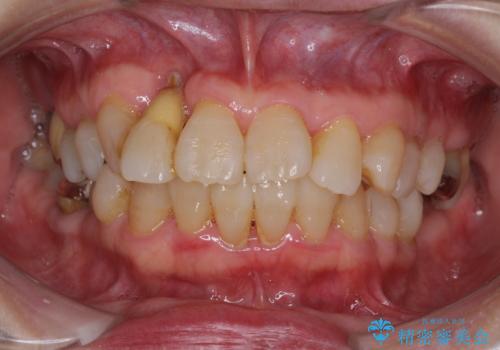

![[MTMを行い歯の神経を保存] 歯周補綴ブリッジの症例 治療前](https://seimitsushinbi.jp/wp/wp-content/uploads/2021/04/21310c2f37874ac2f2ba9939da2fee68-500x350.jpg?v=1618452125)